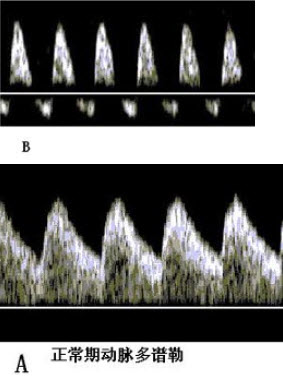

此组图是妊娠胎儿B超声多谱勒期动脉频谱像,图B中S/D值_______,提示_______。

• 此组图是妊娠胎儿B超声多谱勒期动脉频谱像,图B中S/D值_______,提示__